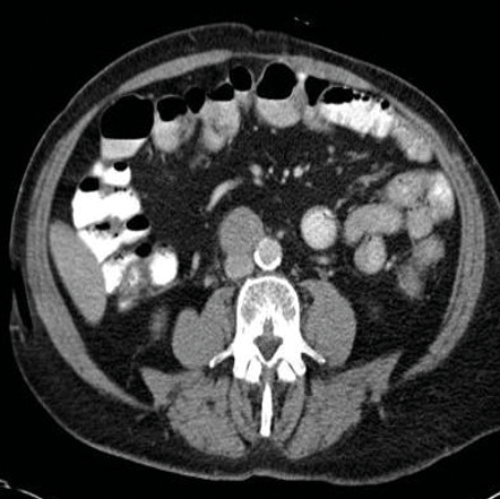

Figure 3. Axial CT showing left para-aortic lymph node from a left sided tumour.

Stage two disease has abdominal lymph nodes; 2a nodes <2cm, 2b nodes 2-5cm, 2c at least one node >5cm. Retroperitoneal lymph nodes are the commonest site for metastatic disease and left sided tumours tend to spread to left para-aortic lymph nodes (Figure 3) and right sided tumours to aorto-caval or precaval nodes [3] (Figure 4). It is important to carefully evaluate the relevant area depending on the site of the tumour.